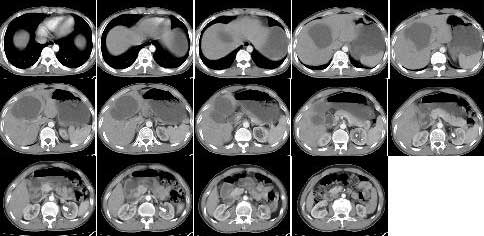

标题: CT5364:肝内囊性病变

m 42 肝内囊性病变2月,之前有多发外伤

如果病史明确,可以考虑外伤性胆汁性肝囊肿。

支持,但要排除肝单纯性囊肿

结合病史考虑外伤性胆汁性肝囊肿

(在受伤时做b超有无异常要是当时没做b超应和先天肝囊肿胆总管囊肿区别)

支持!但单纯囊肿也不能完全除外;另外右肾可见小囊肿;左肾盂示扩张,其内示密度增高影(钙化或造影剂存留,建议对比平扫),考虑左肾盂旁囊肿。

1,胆汁性肝囊肿(外伤性);

2,左肾盂旁囊肿.

不知外伤后有没有查腹部,肝脏有没有外伤性改变,如出血\\挫伤等,如果有的话可考虑为外伤后囊腔形成,至于是胆汁性肝囊肿还是其它性质的囊肿,有待进一步检查;

如果当时外伤后没有查过腹部,或者说肝脏并没有出血挫伤,那么我们所说的只能是猜测而已;

考虑肝囊肿,外伤所致假性囊肿待排。双肾囊肿